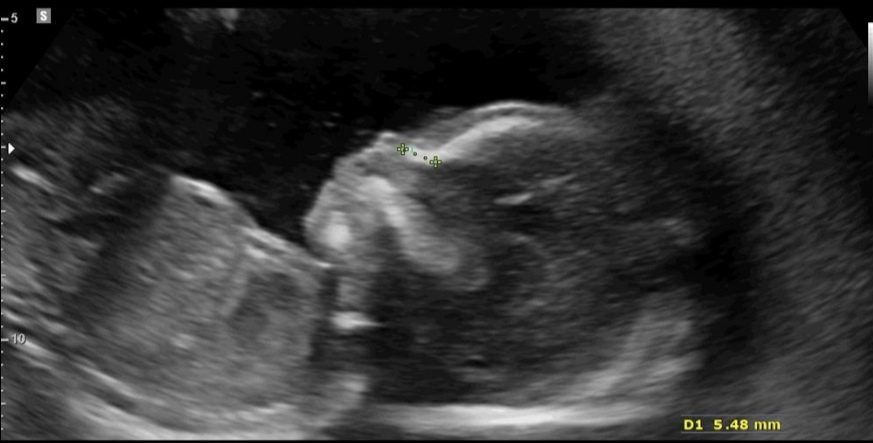

به افتخار دختر قشنگم که بی صبرانه منتظریم صحیح و سالم به دنیا بیاد، نفس مامان من دیشب متوجه شدم خدا به من افتخار داده و داره دنیام رو صورتی میکنه هرچی از بابت خوشحالی این افتخاری که نصیبم شده بگم کم گفتم ان شاالله داخل این مسیری که داری طی میکنی تا برسی پیشه من و بابایی و داداشی خطر ازت دور باشه نفس مامان 🥰😘